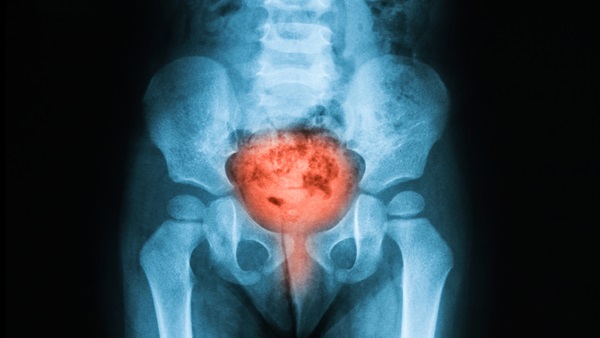

Because there are so many different types of cancers, from basal cell skin cancer to aggressive metastatic brain cancers, each case has to be reviewed individually before a certification decision can be made.

All but the most minimally invasive skin cancers, such as basal or squamous cell, will require FAA review prior to issuance of any class of medical certificate.